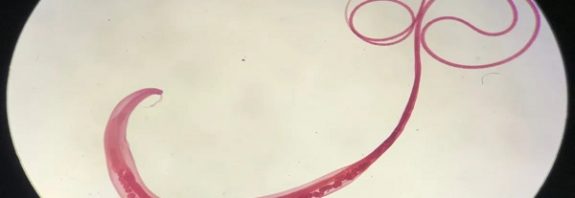

Ancient Viking Poop Shows How Gut Worms Are Humankind’s Closest Companion